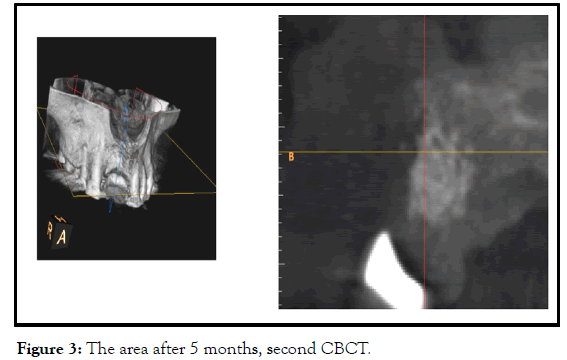

After five months, radiographically, was enough osseous regeneration. In opening to install the implants, portion of the graft was not resorbed, but because of the haemorrhage from the graft, I thought that was integrated, and there was no need for further waiting. osseointegration of the implant does not occur until the grafted bone has become vascularized (Figure 3).